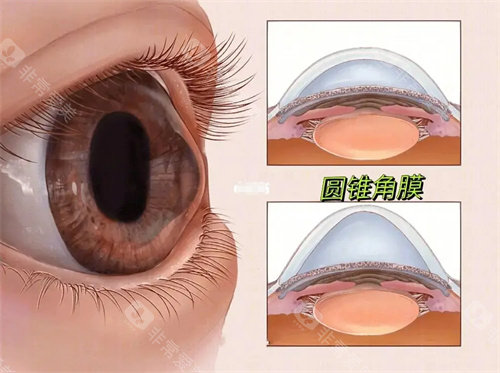

圆锥角膜是一种令人困扰的眼科疾病,而圆锥角膜交联手术为患者带来了希望。